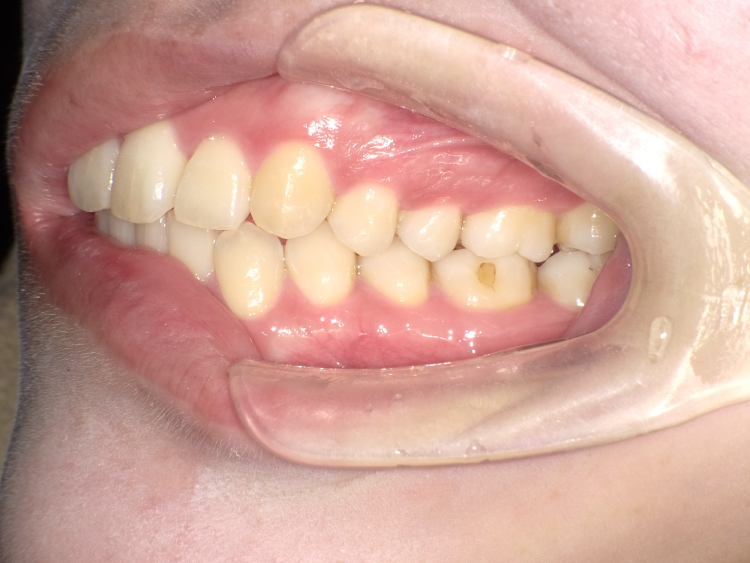

症例2

治療前

治療後

| 主訴 | 上の前歯のガタつきが気になるので前歯だけ綺麗にして欲しい |

|---|---|

| 治療 期間 |

約6ヶ月 |

| 治療費 | 165,000円(税込)/調整費用別途 |

| 治療 内容 |

上の前歯部にワイヤーを着けて進めていく、プチ矯正で施術。 |

| 治療の リスク |

見た目を綺麗にする目的で短期間で仕上げる為噛み合わせは矯正しない。 |